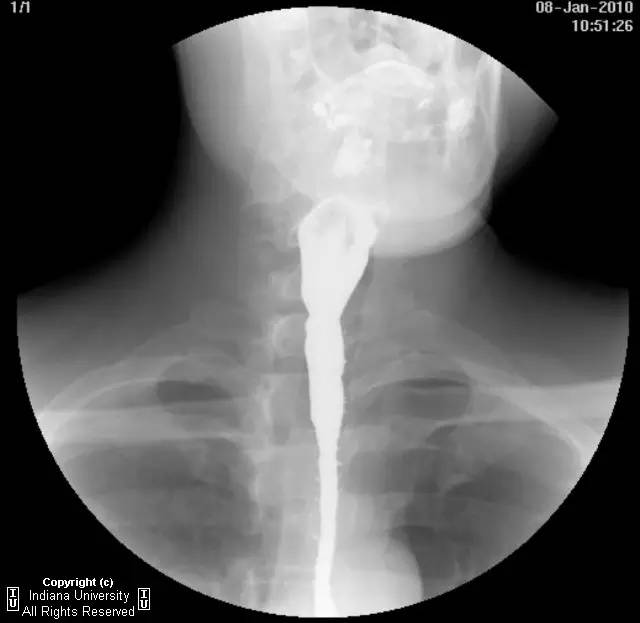

【影像学表现】下咽部正常,环咽肌功能正常。颈段食管无外生性病变压迫或异常扩张。胸中段食管长节段狭窄,逐渐移行为正常食管粘膜。大量小的烧饼样钡斑位于相应食管外呈浮萍样,与食管管腔无直接交通。稠或稀钡剂通过均无延迟。1cm钡剂片延迟通过,约30分钟后自动溶解。余食管动力正常。

【诊断】食管壁内假性憩室并长节段狭窄

Long segmentstricture with esophageal intramural pseudodiverticulosis